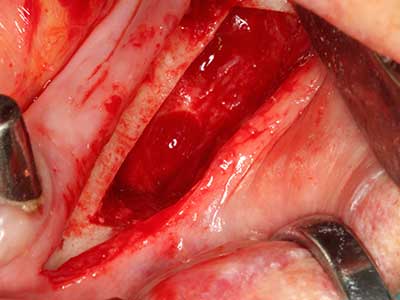

Bei der Knochenblockentnahme zeigen sich weitere Vorteile für die Piezochirurgie: Neben der bereits beschriebenen hohen Präzision bei der Osteotomie stellt sich gerade die Verwendung der dünnen Sägespitzen als besonders materialschonend heraus. Bei der Verwendung insbesondere von Lindemannfräsen sind mit deutlich höheren Entnahmeverlusten durch die dickere Instrumentenspitze zu rechnen (Lakshmiganthan, Gokulanathan et al. 2012). Die insbesondere bei retromolar entnommenen Blocktransplantaten notwendige basale Abtrennung wird durch speziell hierfür vorgesehene rechtwinklige Sägen erleichtert, so dass die Piezochirurgie als präzises, übersichtliches und sicheres Verfahren zur retromolaren Knochenblockgewinnung angesehen wird (Happe 2007) (Abb. 1-12).